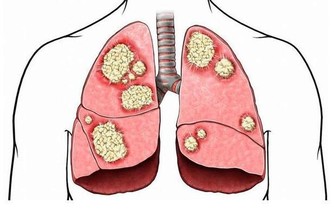

河北省人民醫院婦產科主任醫師秦英教授注意到,得子宮方面疾病的病人多有性格急躁的傾向。雖然目前沒有確切數據顯示情緒對子宮疾病影響的比重,不過緊張、發脾氣常造成內分泌失調,內分泌失調後,身體各器官都會受影響,而生殖系統和激素關係最密切,因此損害更加明顯,如子宮肌瘤、乳腺增生症的發生就是雌激素水平過高所致。

中醫也有類似說法,子宮在肝經上,如果脾氣急躁,久而久之,肝鬱氣滯、氣滯血瘀,就容易生子宮肌瘤,引起卵巢功能衰退。再加上女性本身就比男性更加情緒化,因此更要保持愉快心情,少生氣才能收穫健康。

生悶氣特別容易對乳房健康產生影響。特別愛生氣的人容易出現乳腺增生,是因為乳房處於“肝經所過”之地,生悶氣傷肝,肝氣不出,容易鬱結,肝氣鬱滯,痰阻血瘀,輕則胸脅脹痛,重則血瘀痰阻成為結節,經絡運行受阻,自然易長結節。